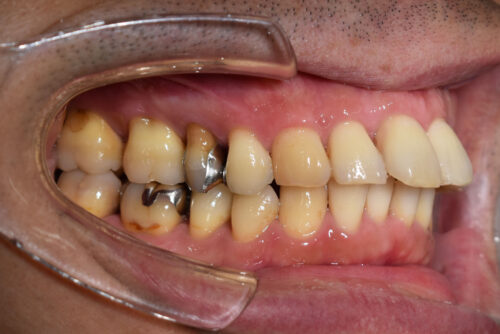

本症例も

下顎左側第二小臼歯欠損

上下とも歯が唇側に傾斜し

出っ歯も呈しておりました。

非抜歯矯正治療計画で

下顎は

ご自身の歯で かめるように

歯の欠損部は

全てスペースを閉じる

非抜歯矯正治療を開始しました。